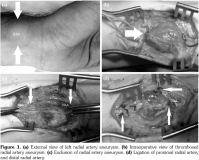

domination of the ulnar supply to the palmar arch. A Doppler ultrasound revealed 10x12 cm hematoma in his right thigh, acute thrombosis in his right common femoral vein, and true saccular RAA. Routine preparation for surgery was made and a written informed consent was obtained from the patient. Under local anesthesia, the aneurysm site was incised. A 2x2 cm saccular aneurysm was excised at the distal part of the radial artery (Figure 1). The histopathological report showed clusters of lymphocytes neutrophils, plasma cells, fibrin infiltration, and destruction in the intima and medial layer of the arterial wall. The postoperative course was uneventful and he was discharged with oral anticoagulation and oral prednisolone at 25 mg twice daily.